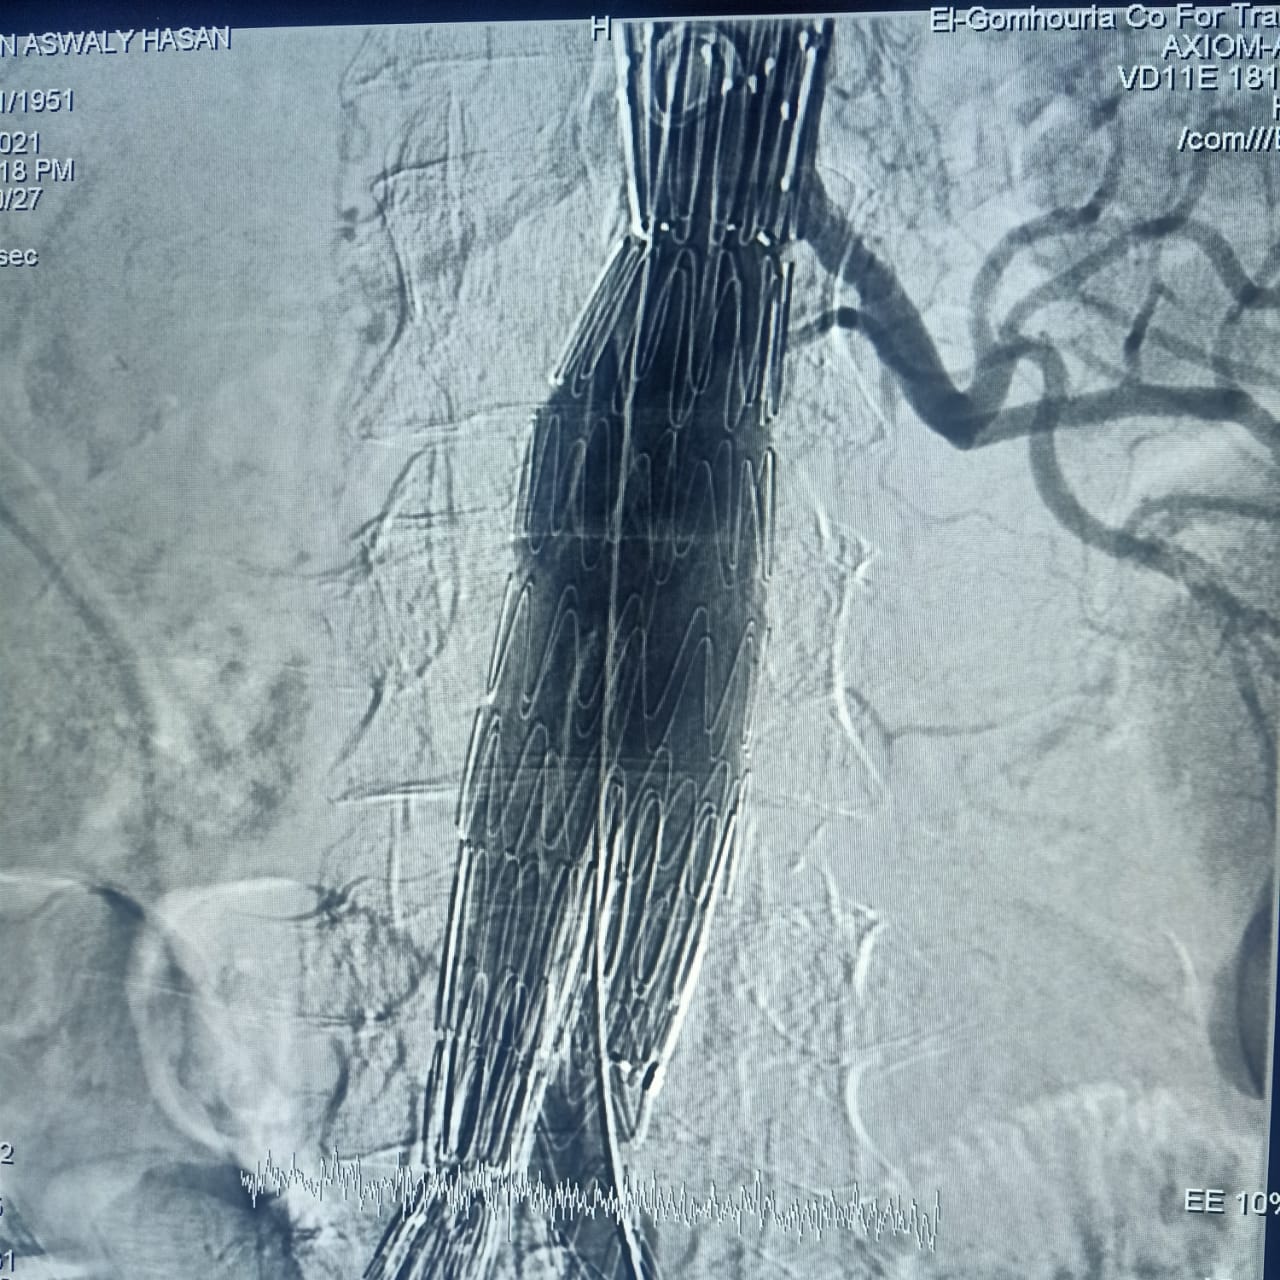

وأشارت هيئة الرعاية الصحية، أن CERAB، EVAR هي من أحدث التقنيات العلاجية لأمراض تمدد وانسداد الشريان الأورطي البطني والحرقفي (بدون جراحة)، من خلال علاج تمدد الشريان الأورطي البطني عن طريق القسطرة باستخدام تقنية الدعامات المغطاة EVAR، وكذلك علاج انسداد الشريان الأورطي البطني والحرقفي عن طريق القسطرة باستخدام تقنية الدعامات المغطاة ذات المقاومة العالية للانسداد CERAB، وذلك وفقًا لأحدث ممارسات الصحة العالمية.

وأضافت الهيئة، أن عمليات علاج تمدد وانسداد الشريان الأورطي البطني والحرقفي عن طريق القسطرة التداخلية بدون جراحة، تساهم في الحفاظ على حياة وسلامة المرضى وعلاجهم بطريقة أكثر أمانًا وفق أحدث الإرشادات والبروتوكولات العلاجية المعتمدة دوليًا، حيث أنها تقلل من نسبة تعرض المريض للأعراض الجانبية المحتمل حدوثها عند اللجوء للحل الجراحي المعتاد بما تحمله جراحة الشرايين من خطورة على القلب وأخذ وقت طويل لإتمام الشفاء فضلًا عن عدم صلاحيتها لعلاج كل الحالات، وخاصة في حالات المرضى من كبار السن.

وتابعت الهيئة: أن العملية الأولى كانت لعلاج مُسِّن يبلغ من العمر 70 عامًا يعاني من تمدد بالشريان الأورطي البطني وتم علاجه باستخدام تقنية الدعامات المغطاة EVAR، بينما كانت العملية الثانية لعلاج مريض يبلغ من العمر 65 عامًا باستخدام تقنية الدعامات المغطاة المقاومة للانسداد CERAB، مشيرة إلى استقرار الحالة الصحية للمريضين وإجراء العمليات بنجاح على يد أمهر الأطقم الطبية والتمريضية في مستشفى طيبة التخصصي بالأقصر.